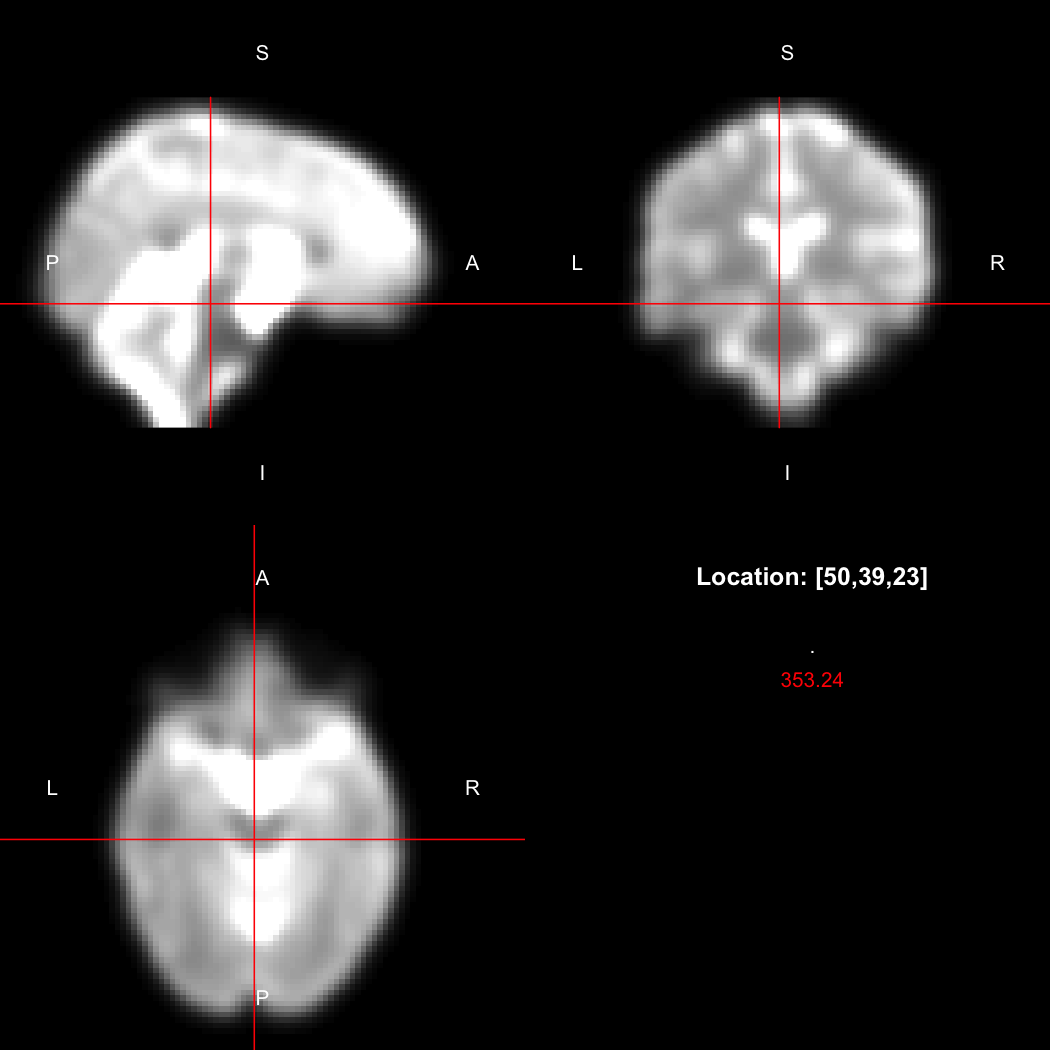

However, the pipe syntax provides an alternative, which can be further simplified because calling view() on a pipeline will implicitly run it.

image %>% smooth_gauss(4) %>% view()

## Setting window to (0, 549.9)

plot of chunk pipe

Notice now smooth_gauss() is now called with only one argument, and view() with none, because the input to the pipe (%>%) is implicitly added first. The benefits to readability of this approach increase substantially as more operations are added to the chain: